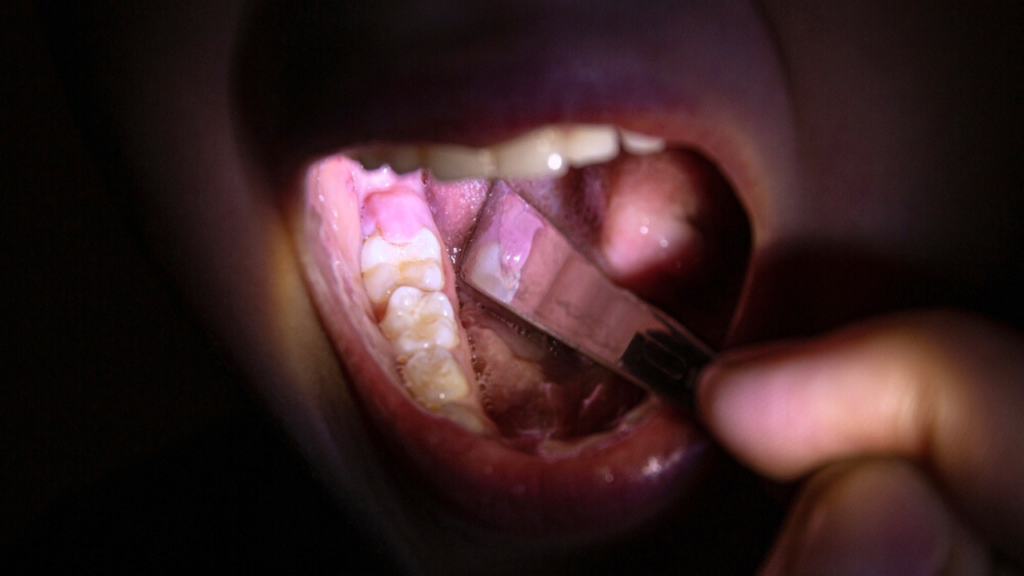

Fondamentalement, cela s'applique aux troisièmes molaires, qui éclatent la toute dernière - après 17 ans, et pour beaucoup ce processus passe par diverses complications La péricoronarite est une inflammation des gencives autour d'une dent qui n'a pas complètement émergé, généralement une dent de sagesse

Source: eyeluxeru.pages.dev La péricoronarite des informations importantes , La péricoronarite est un trouble dentaire causé par une inflammation et une infection de la gencive qui recouvre une dent partiellement sortie, causant de la douleur et une gêne qui peut rendre difficile le fait de manger, d'avaler ou d'ouvrir ou de fermer la bouche Une péricoronarite est une inflammation de la gencive qui se situe autour de la couronne.

Source: pbpbfftw.pages.dev Pericoronarite O Motivo Pelo Qual o Seu Dente do Siso Dói Tanto Arriba Dentista , Une péricoronarite est une inflammation de la gencive qui se situe autour de la couronne d'une dent La péricoronarite est un trouble dentaire fréquent chez les adolescents et les jeunes adultes.Globalement, elle correspond à une inflammation des tissus entourant une dent.Si elle n'est pas soignée, la péricoronarite peut entraîner des complications graves dont la redoutable cellulite cervico-faciale.